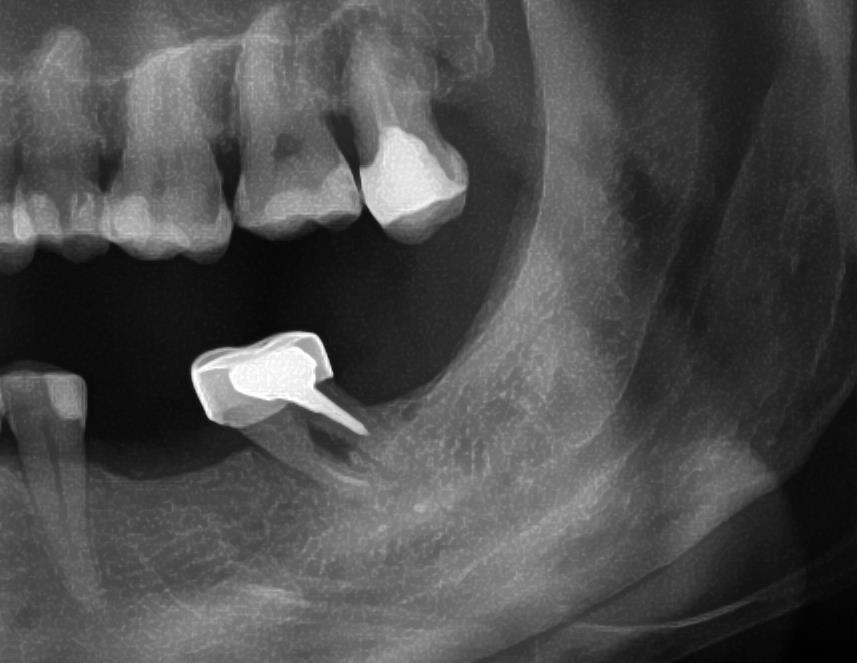

Не каждый зуб можно вылечить. Бывают ситуации когда приходится удалять зуб, находящийся в линии улыбки. В этом случае, для того чтобы не пострадала эстетика, применяется метод имплантации, проводящийся одномоментно с удалением зуба. Вкратце: зуб удаляется, в лунку удаленного зуба устанавливается имплантат, на имплантат устанавливается временная пластиковая коронка. В этом случае пациент не испытывает дискомфорта с эстетической точки зрения. Спустя 4-6 месяцев временная коронка может быть заменена на постоянную, высоко эстетичную реставрацию. Процедура требует от врача имплантолога очень аккуратной работы, знаний и опыта как в имплантологии так и в области ортопедии.